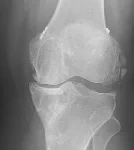

İncelemeler: USG'de minimal suprapatellar efüzyon. MCL heterojen görününde fibrillar yapı bozulmuş. Direkt grafi ve MRG'leri ektedir.

Resim 1. Resim 1. Direkt grafi.